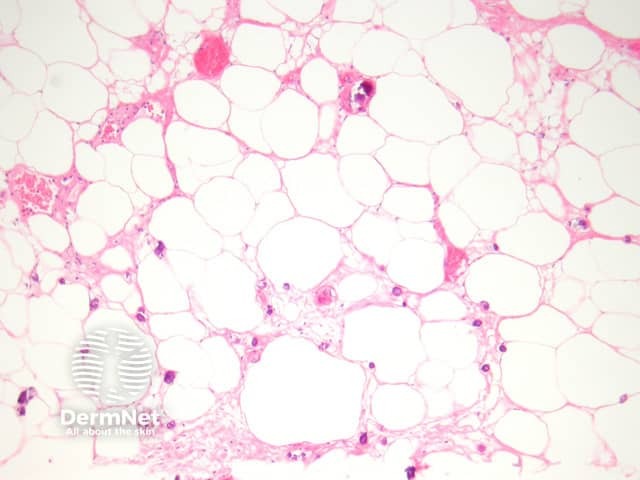

A deep biopsy to sample the subcutis is needed to make the diagnosis of calciphylaxis. The epidermis and dermis is often ulcerated and necrotic with numerous secondary changes (figure 1). There is calcification of small-medium sized vessels (figures 2-3). The intima of the vessels is commonly fibrosed and there may be intravascular thrombi. Diffuse calcification of small capillaries in the fat is a characteristic feature (figure 3). There may also be calcification of adipocytes.

Calcium can be demonstrated with special stains such as Von Kossa.